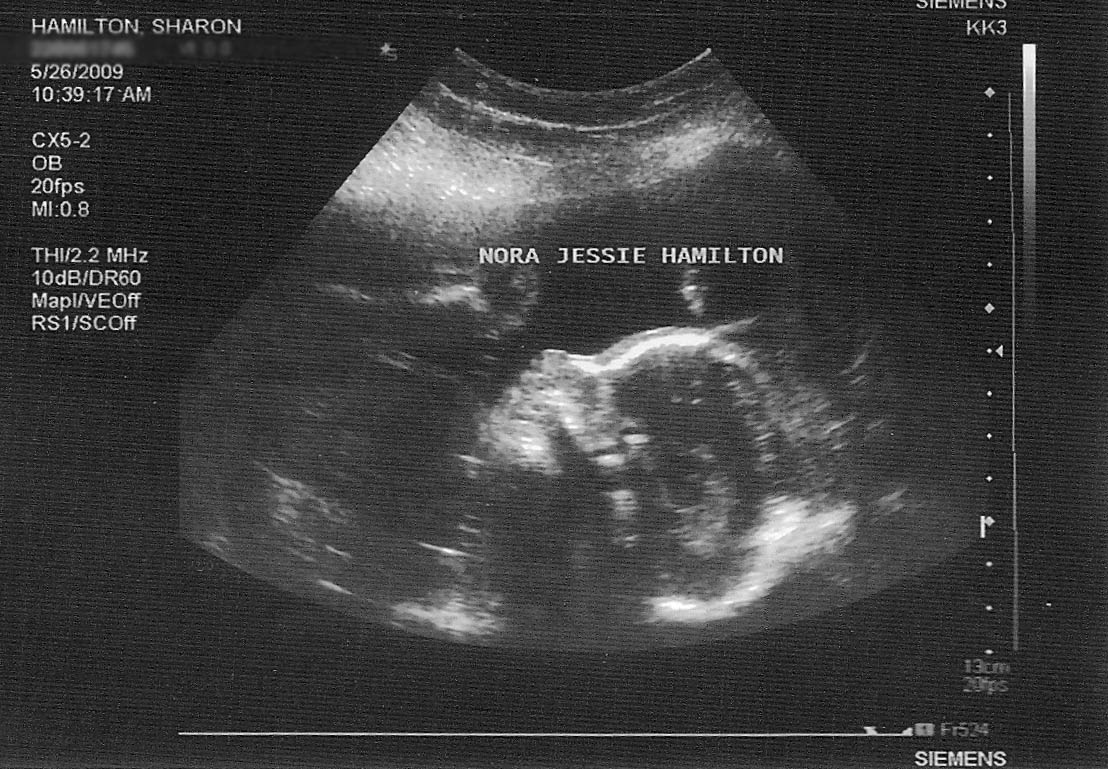

We had another ultrasound and checkup yesterday to monitor the progress of Nora and the pregnancy. All is going well, nothing much to report which is a good thing at this point. “No Gnews is good Gnews”. (anyone know where that quote is from? 🙂 But one thing we have been increasingly noticing with Nora is that she moves alot. She gave the ultrasound tech a run for her money when she was trying to examine her and take measurements. It is so cool to watch her move in there. She used her hands to shield her face at times, she kicked at the probe. It was quite amusing. But on the other hand, is this a precursor to what is to come. Is she going to be a restless child and not sleep a lot, instead always wanting to play and be doing stuff? Not sure if the movement in the womb equates to how they are as babies. If anyone has an experience to share or knowledge on the subject I would be curious to hear about it.